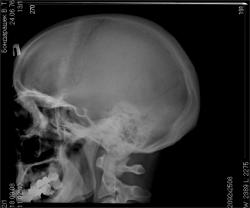

Проведенные нами «первые» рентгенографические исследования с использованием Система компьютерной радиографии Point-of-Care СR 120 показали, что объективно диагностика, с учетом анализа скиалогической картины «вышла» на новый качественный уровень. В качестве иллюстрации мы приводим возможности цифровой обработки, полученного изображения черепа. Как известно на классической рентгенограмме черепа (боковой) удовлетворительно дифференцируются только кости, образующие  мозговой череп. Шейный отдел позвоночника и мелкие детали не визуализируются в результате естественной физико-технической (с учетом кВ и мАs) переэкспонированности.

На иллюстрации 4 представлено «первично полученное» изображение черепа в боковой проекции. Снимок удовлетворительного качества, хорошо визуализируется «зона физиологического склероза» в. области лобно-теменного шва.